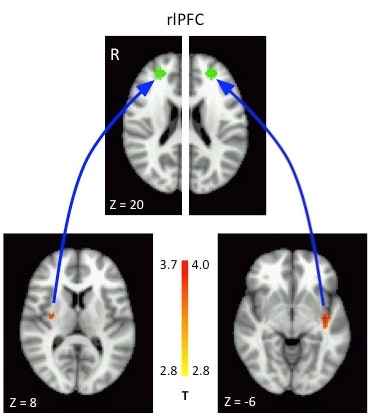

Specifically, the researchers uncovered a stronger connection between the rostrolateral prefrontal cortex and the posterior insula and putamen in the brains of subjects who tended to explore. The rostrolateral prefrontal cortex has also been associated with a tendency to explore in adults.

When two groups were compared, fMRI showed a stronger connection in the explorers between the rostrolateral prefrontal cortex and the posterior insula and putamen regions of the brain.

In addition, activity in the putamen and insula seemed to influence the rostrolateral prefrontal cortex, rather than the other way around.

The researchers speculated that the posterior insula and putamen were involved because the insula may influence uncertainty and the putamen may reflect the success of other reward-related action plans.